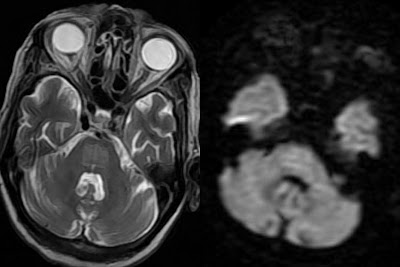

Cerebral White Matter Hyperintensities On MRI: Current ...

Cerebral White Matter Hyperintensities on MRI: Current Concepts and Therapeutic Implications Bruce Ovbiagele Jeffrey L. Saver ischemic demyelination and gliosis, and occasionally to clinically silent infarcts [17] . Chronic low-grade vascular ... Read Document